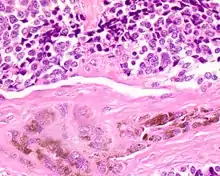

Microscopic

The tumor is usually very well circumscribed but not encapsulated. There are two cell types present (biphasic), arranged in alveolar or tubular configurations.

There are centrally located, small, darkly staining cells comprising the majority of cells. These cells have a fibrillary cytoplasm surrounding round nuclei with coarse and heavy nuclear chromatin. These cells are surrounded by much larger polygonal cells that have open nuclear chromatin and abundant opaque cytoplasm that has granular melanin pigment.

There is usually no hemorrhage, necrosis or increased mitoses.[1][4]